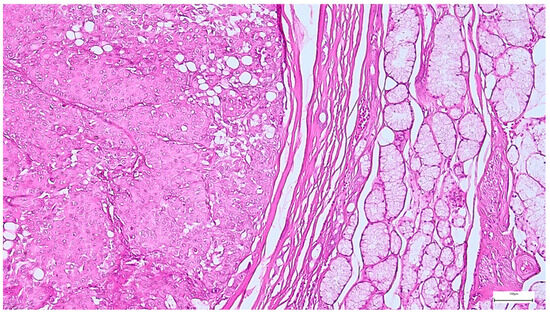

On gross examination, most pleomorphic adenomas appeared as well-demarcated, bosselated, gray-white myxoid masses. Intraoperative salivary imprint cytology was applied if tumors contained areas of necrosis, hemorrhages, or infiltrative margins. Tumor sizes ranged from 9 to 82 mm, with a mean diameter of 32.55 ± 13.38 mm. Histological examination of pleomorphic adenomas revealed the characteristic biphasic epithelial–myoepithelial architecture. The tumors displayed a heterogeneous cellular composition (248 cases; 98.02%), while the pleomorphic adenoma oncocytic subtype was identified in five cases (1.98%) (Table 3). The stromal component exhibited marked variability, the myxoid phenotype being the predominant pattern (138 cases; 54.54%), followed by chondromyxoid phenotype (72 cases; 28.45%) (Figure 4 and Table 3).

Figure 4. Multinodular, biphasic tumor cells proliferation, embedded in a chondromyxoid stroma and surrounded by a thin hypocellular fibrous capsule in pleomorphic adenoma (H&E staining, 5×).